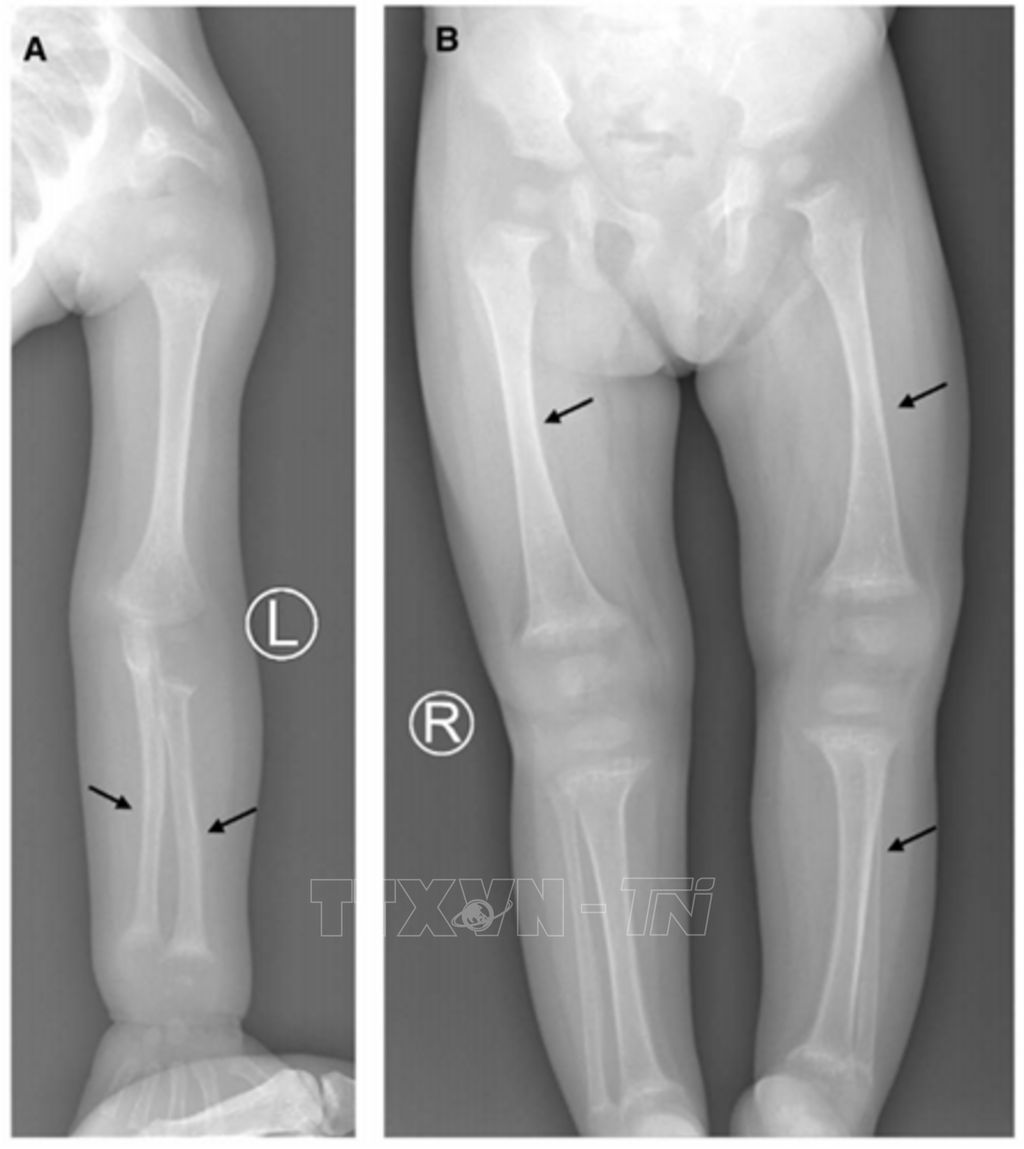

Tại Việt Nam, đã có khoảng 100 loại bệnh hiếm được báo cáo và gây ảnh hưởng đến khoảng 6 triệu bệnh nhân; tuy nhiên, dữ liệu di truyền liên quan đến các bệnh hiếm như loạn sản xương, rối loạn phát triển giới tính, suy tuyến yên bẩm sinh,… còn rất hạn chế. Do sự chồng lấp về triệu chứng giữa các bệnh lý khác nhau, việc chẩn đoán bằng các phương pháp lâm sàng và xét nghiệm thông thường gặp nhiều hạn chế, đặc biệt đối với các bệnh hiếm có căn nguyên di truyền.

Xuất phát từ thực tiễn trên, Giáo sư, Tiến sỹ Nguyễn Huy Hoàng, Phó Viện trưởng Viện Sinh học, Viện Hàn lâm Khoa học và Công nghệ Việt Nam và nhóm nghiên cứu của Viện Sinh học đã thực hiện đề tài “Nghiên cứu đột biến gen ở các bệnh nhân người Việt Nam mắc một số bệnh hiếm gặp bằng công nghệ giải trình tự gen toàn bộ vùng mã hóa”, đề tài cấp Viện Hàn lâm, được thực hiện từ năm 2022 - 2024, với mục tiêu làm sáng tỏ căn nguyên di truyền của các bệnh hiếm gặp này trên quần thể người Việt Nam.